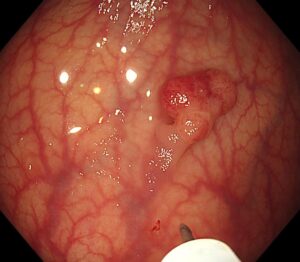

👉 局注針を内視鏡から出します(写真2)

(写真2)